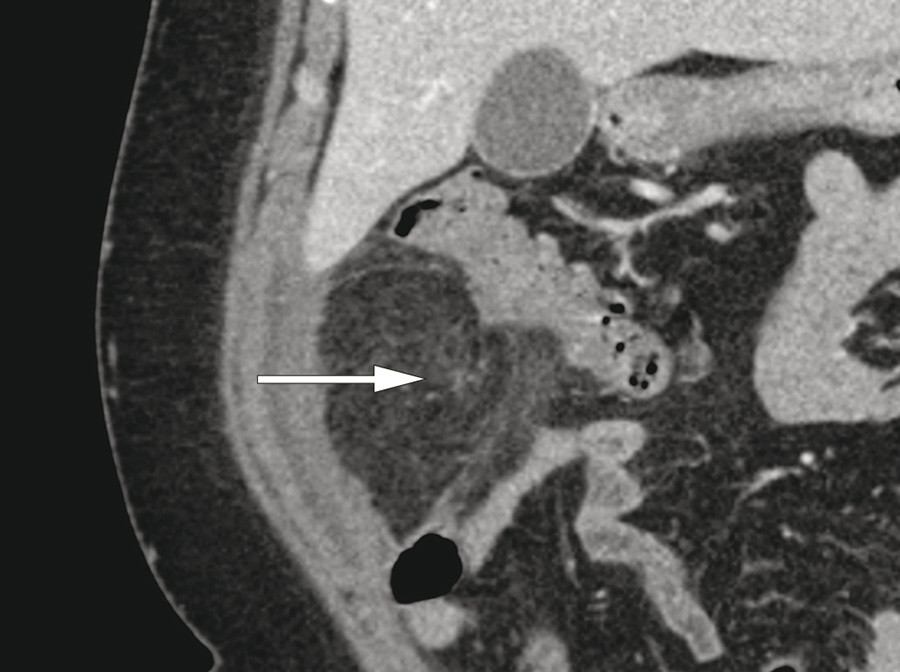

En kvinne i 40-årene ble innlagt med magesmerter, mest uttalt under høyre kostalbue. Smertene var konstante og hadde oppstått tre dager tidligere. Hun var ikke tidligere operert i buken. Ved klinisk undersøkelse var abdomen bløt med palpasjonsømhet i øvre høyre kvadrant. Bortsett fra forhøyet CRP på 80 mg/l (< 5) var alle blodprøver normale. Ultralydundersøkelse av lever, galleblære og pancreas ved innkomst viste upåfallende forhold. På grunn av vedværende sterke smerter ble pasienten undersøkt med CT abdomen samme dag. CT-undersøkelsen viste et avkapslet område av mesenterialt fettvev ventralt i øvre høyre kvadrant. I koronalplan (bilde til venstre) indikerer pilen det avkapslede området. I sagittalplan (bilde til høyre) så man tydelig en spiralformet forandring, som kunne representere roterte kar og mesenteriale strukturer (pil). Pasienten ble laparoskopert og det ble funnet en partiell torsjon av omentum majus. Det torkverte segment lå adherent mot bukveggen og inneholdt begynnende nekrotiske forandringer og ble fjernet.